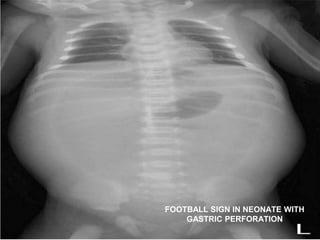

FOOTBALL SIGN IN NEONATE WITH

GASTRIC PERFORATION